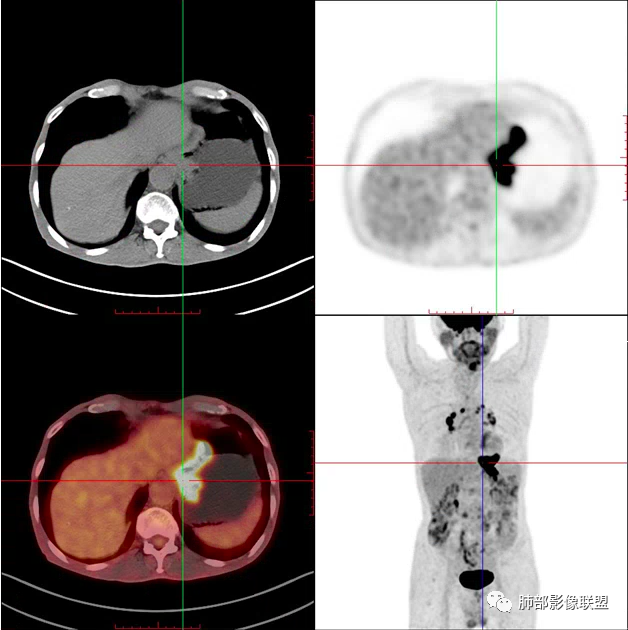

男,83,前胸部隐痛不适1月。有长年大量吸烟史。胸部CT:肺气肿,右肺下叶纺锤型实性结节灶,边界清晰,支气管截断,内部密度不均匀,增强扫描不均匀强化,右肺门淋巴结大。考虑恶性病变:小?鳞?鉴别炎性肉芽肿、错构瘤等。

病理结果:小细胞肺癌

2娘小崽大、淋巴及血行转移早、冰冻纵隔及肺门、血管脂肪间隙消失

因为病灶侵袭力强,病灶易沿淋巴道、间质及心血管间隙等结构侵犯并密切挤压上述结构,常常能够观察到脂肪间隙消失。易于出现冰冻纵隔。原发灶与肺门转移灶可形成哑铃状外观,甚至转移灶体积大于周围原发灶,有人称之为“娘小崽大”。早期病灶有时很小甚或隐匿,仅能看到转移灶,或转移淋巴结与原发灶融合分界不清。病变向肺门延续的串珠样淋巴结转移也是SCLC的典型特点。